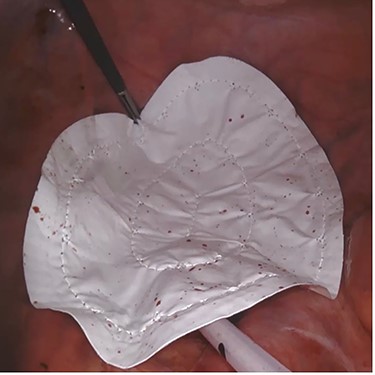

A 42-year-old man with perianal abscess and fistula due to low rectal cancer had completed long-course radiotherapy but was unable to complete FOLFIRI regimen due to elevated liver enzymes because of his underlying chronic hepatitis B. He underwent robotic-assisted abdominoperineal resection (APR) 6 weeks later. Mesh placement was performed laparoscopically after placing transabdominal pelvic drain (Fig. 1). He developed perineal wound infection on postoperative day 4 requiring wound dressings and antibiotics. He was discharged 17 days after surgery but was readmitted 28 days after initial operation for presacral abscess requiring percutaneous drainage. Subsequent CT abdomen showed resolution of presacral collection. Histopathological examination showed moderately differentiated adenocarcinoma ypT3N0M0. He completed adjuvant capecitabine and after 12.5 months, there was no evidence of unhealed perineal wound or small bowel descent.

Case 2—laparoscopic picture of Gore-Tex Dual Mesh placed at the pelvic inlet with the microporous smooth side facing the abdominal cavity.